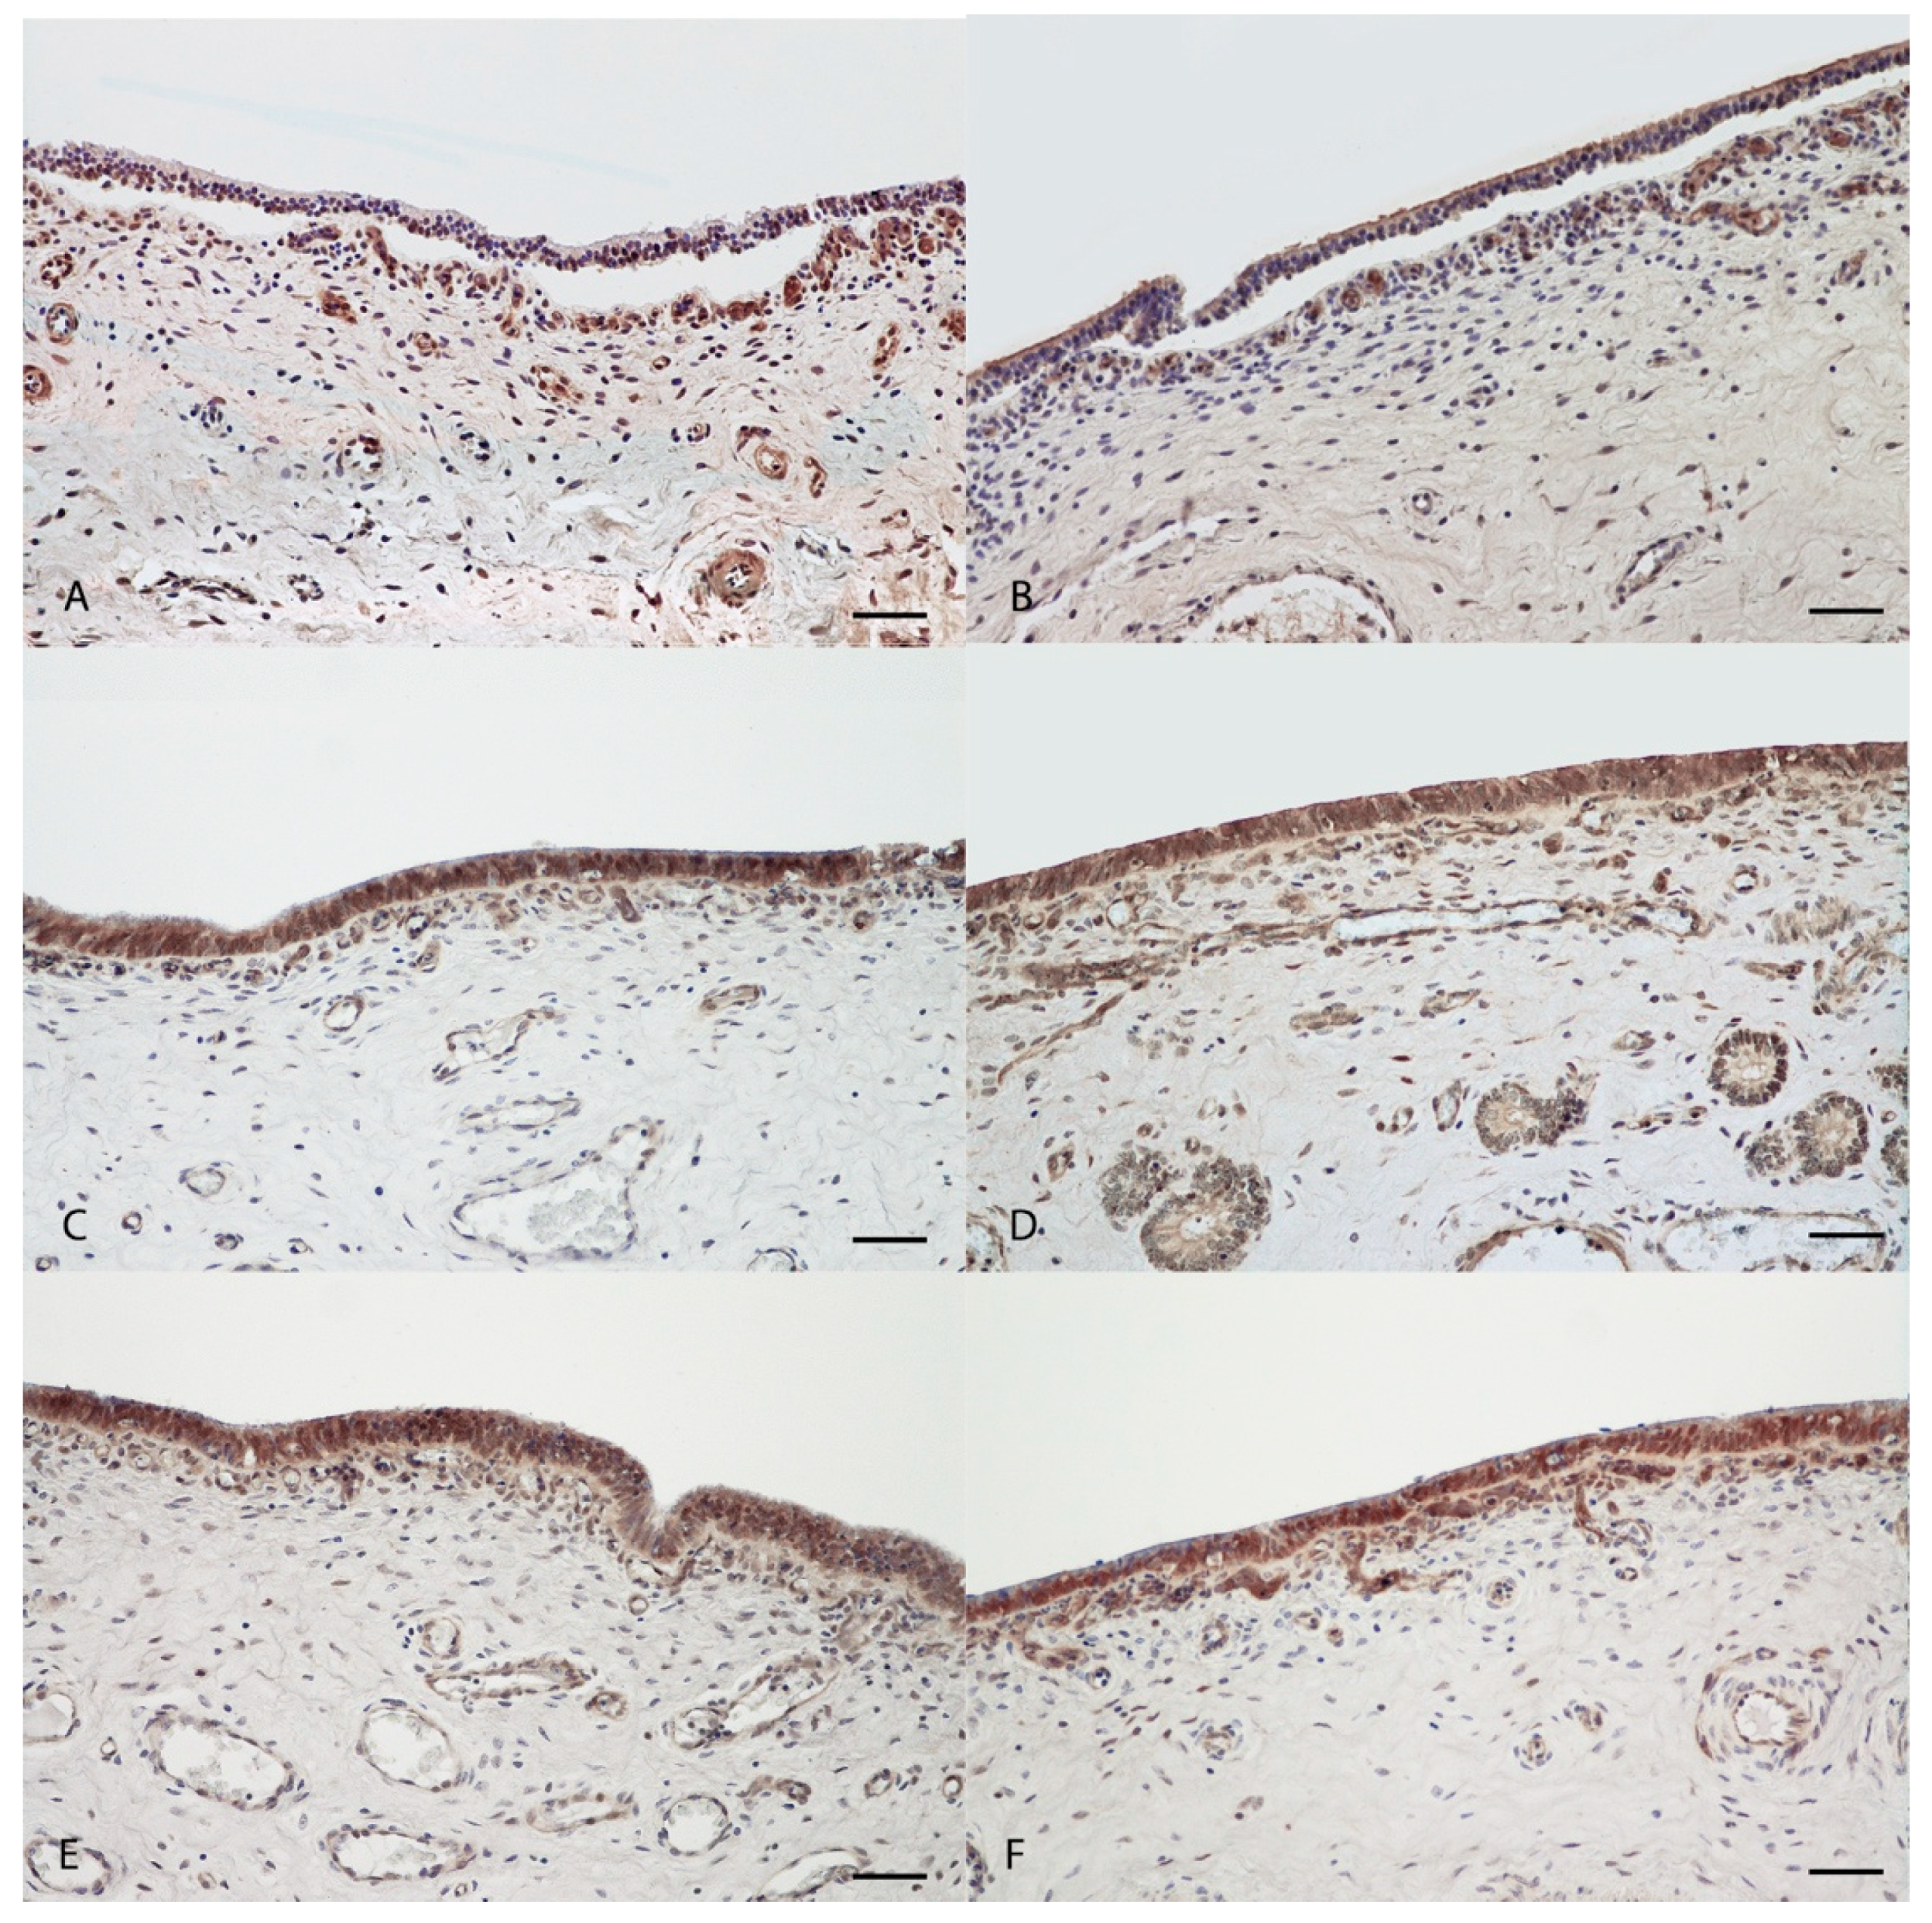

Figure 4.

Immunohistochemical assessment of ZO-1 expression in porcine uterine mucosa incubated in vitro with Melaleuca alternifolia and Rosmarinus officinalis essential oils. Tissue incubated with concentration of 500 mg/mL (positive control) Ma (A) show lacking antibody expression within mucosal epithelium; tissue incubated with concentration of 500 mg/mL (positive control) Ro (B) show mild and rare positive expression of epithelial cells. Tissues incubated with 0.4 mg/mL (C, Ma and D, Ro) and 0.2 mg/mL (E, Ma and F, Ro) concentrations of both oils revealed intense and diffuse cytoplasmic expression of ZO-1 protein within mucosal epithelium. 200×. Bar = 50 µm.

Immunohistochemical analyses revealed mild to absent expression of ZO-1 within detached mucosal epithelium of positive control samples incubated with 500 mg/mL of both EOs (Figure 4A,B), while the expression was intense and present in epithelial cells of samples treated with all other concentrations of both EOs, regarding in vitro and ex vivo assays (Figure 4 and Figure 5) including in negative control with emulsifiers only (Figure S1B). Upon immunofluorescence, expression of ZO-1 was comparably mild to absent in epithelial cells of uterine samples treated with 500 mg/mL concentration (positive control) of both EOs (Figure 6A,B,I,J, Ma and Ro, respectively) and moderately intense but diffused in those treated with 40 mg/mL concentration of both EOs. The 0.4 and 0.2 mg/mL concentrations, in both in vitro and ex vivo assays, did not show any remarkable alterations in ZO-1 expression when compared to control samples (Figure 6).